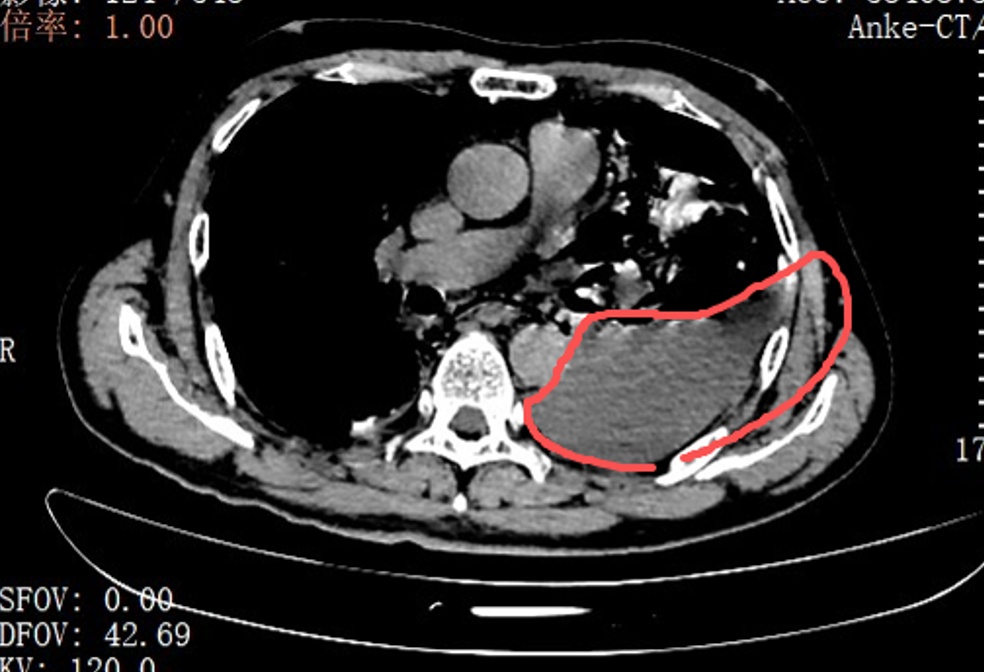

多学科联动10厘米裂口被成功修补

确诊后,胸外科手术团队当天即为张叔实施了胸腔镜下食道修补微创手术。打开胸腔后,眼前的一幕让医护人员震惊:整个左侧胸腔内充斥着叉烧包的菜叶、食物残渣,与脓液、消化液混合在一起。

红圈区域是食物残渣、消化液破入食管